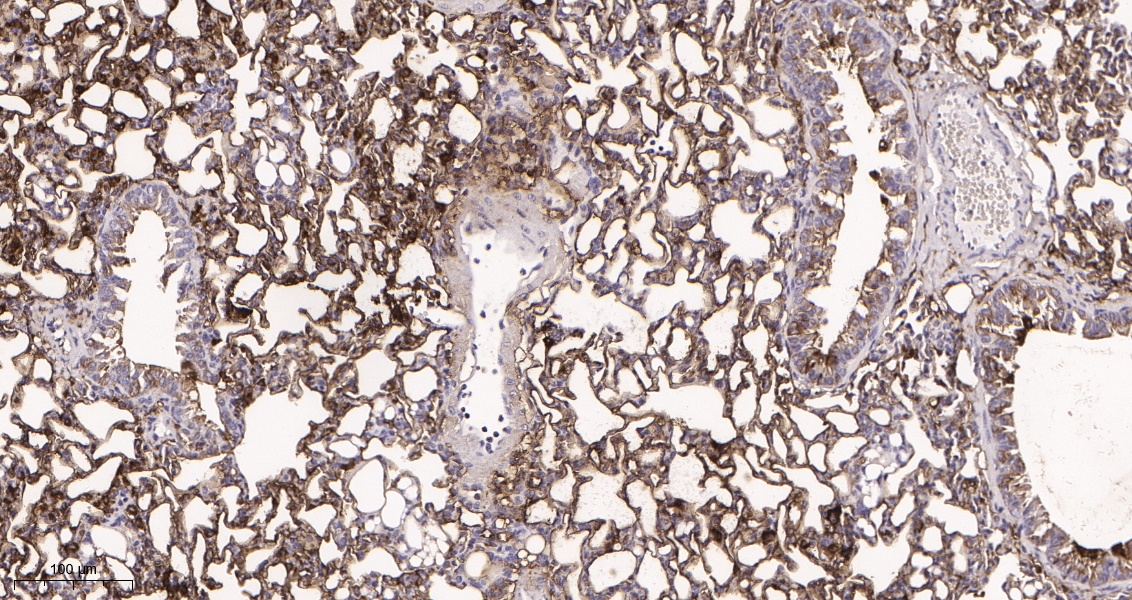

产品名称PKM (3J2) Rabbit Monoclonal Antibody

推荐应用WB,IHC-P,IF-P,IF-F,IF-ICC,ELISA

稀释度IHC-P 1:200-1000, WB 1:1000-5000, IF-P/IF-F/IF-ICC 1:200-1000, ELISA 1:5000-20000

背景介绍This gene encodes a protein involved in glycolysis. The encoded protein is a pyruvate kinase that catalyzes the transfer of a phosphoryl group from phosphoenolpyruvate to ADP, generating ATP and pyruvate. This protein has been shown to interact with thyroid hormone and may mediate cellular metabolic effects induced by thyroid hormones. This protein has been found to bind Opa protein, a bacterial outer membrane protein involved in gonococcal adherence to and invasion of human cells, suggesting a role of this protein in bacterial pathogenesis. Several alternatively spliced transcript variants encoding a few distinct isoforms have been reported. [provided by RefSeq, May 2011].